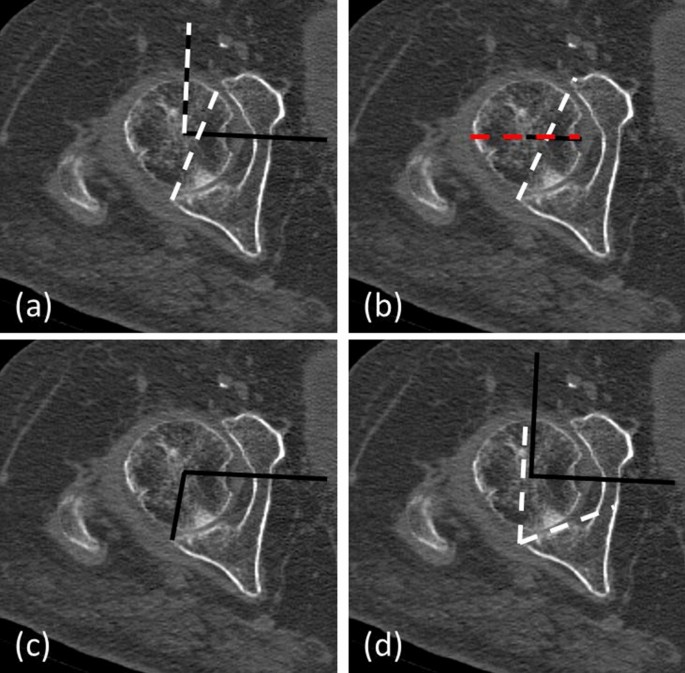

Polyethylene wear and spino-pelvic imbalance were determined on postoperative radiographs. Radiological evaluation of CT-scans was performed by a trained orthopaedic surgeon (PG), who was blinded to patients’ group allocation. Acetabular anteversion angle (AAA), posterior acetabular sector angle (PASA), posterior wall angle (PWA), and acetabular roofing (%) were evaluated from CT scans. Methodology described by Fullam et al. [15] was used for radiological evaluation. In short, an inter-capital centre line (ICL) was drawn on true axial images through both femoral heads at the point of maximum diameter in all 3 planes. An orthogonal line to the ICL—the ICL90 was drawn. A line between the anterior and posterior acetabular lip of the acetabulum was drawn the anteversion line (AVL). The angle between the ICL90 and AVL was measured to determine the AAA. The PASA was determined as described by Valera et al. [17] i.e. by measuring the angle between the ICL and a line from the femoral head centre to the lateral edge of the posterior wall. The PWA was measured by using the angle between the ICL90 and the tangent to the posterior articular surface area. The femoral head coverage/roofing was determined using the ICL and AVL. The part within the acetabulum to the AVL was divided by the whole femoral head diameter to determine the amount of femoral head coverage (% of total) (Fig. 1).

Radiological measurements: a in short, an intercapital centre line (ICL) was drawn on true axial images through both femoral heads at the point of the largest diameter in all 3 planes. An orthogonal line to the ICL the ICL90 was drawn. A line between the anterior and posterior acetabular lip of the acetabulum was drawn the anteversion line (AVL). The angle between the ICL90 and AL was measured to determine the AAA. b The femoral head coverage was determined using the ICL and the AVL. The part within the acetabulum to the AVL was divided by the whole femoral head diameter. c The PASA was determined as described by Valera et al. measuring the angle between the ICL and a line from the femoral head centre to the lateral edge of the posterior wall [17]. d The PWA was measured by using the angle between the ICL90 and the tangent to the posterior articular surface area (color figure online)